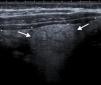

Se realiza una ecografía abdominal (fig. 1), apreciándose, en la zona del dolor selectivo, hiperecogenicidad de la grasa intraabdominal. Apéndice vermiforme normal.